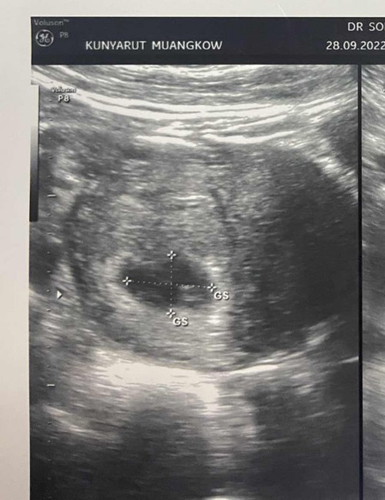

กลัวเสี่ยงท้องลมจังเลยค่ะ

ไม่เเน่ใจว่าตัวอ่อนรึป่าว หมอก็ยังไม่ยืนยันว่าใช่ไหม ก็ยังพุดว่ายังไม่พบตัวอ่อน กลัวท้องลมจังเลยค่ะ😰